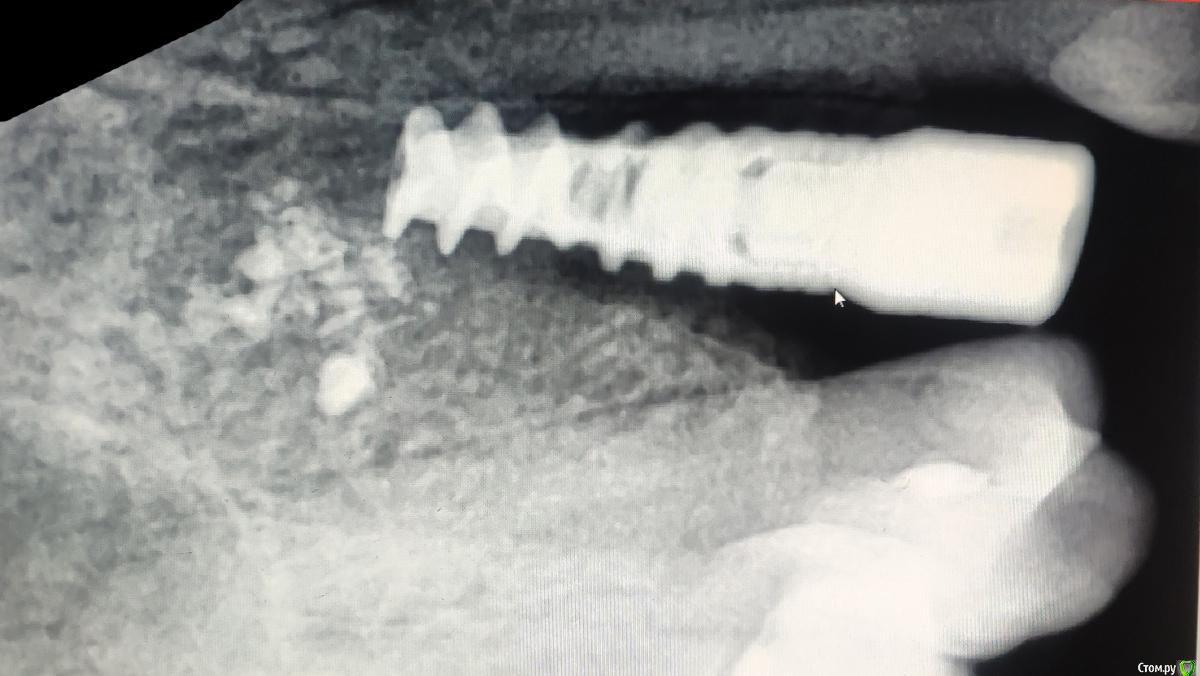

zumanok Опубликовано 27 марта, 2019 Поделиться Опубликовано 27 марта, 2019 Здравствуйте доктора. Прислали снимок, имплантат альфа био, что делать?После установки прошло 3 мес. Опыт в имплантации не особо большой, но мне кажется что имплантат лучше извлечь. Хотелось бы послушать ваше мнение.Удалить, засыпать графт, и через 3 месяца переустановить? Или еще поживет? Ссылка на комментарий

Дмитрий Л. Опубликовано 28 марта, 2019 Поделиться Опубликовано 28 марта, 2019 Возможно это было удаление с немедленной имплантацией в лунку, имплантат заякорили верхушкой и присыпали остеопластическим материалом. Лунка зуба объясняет просветление костной ткани. Но с одной стороны всё-же есть кратерообразная резорбция, напоминающая периимплантит.В любом случае, смотрите на цвет слизистой и кровоточивость, и учитывайте что три месяца для одномоментной альфабио это мало, сильно не шатайте там. 1 Ссылка на комментарий